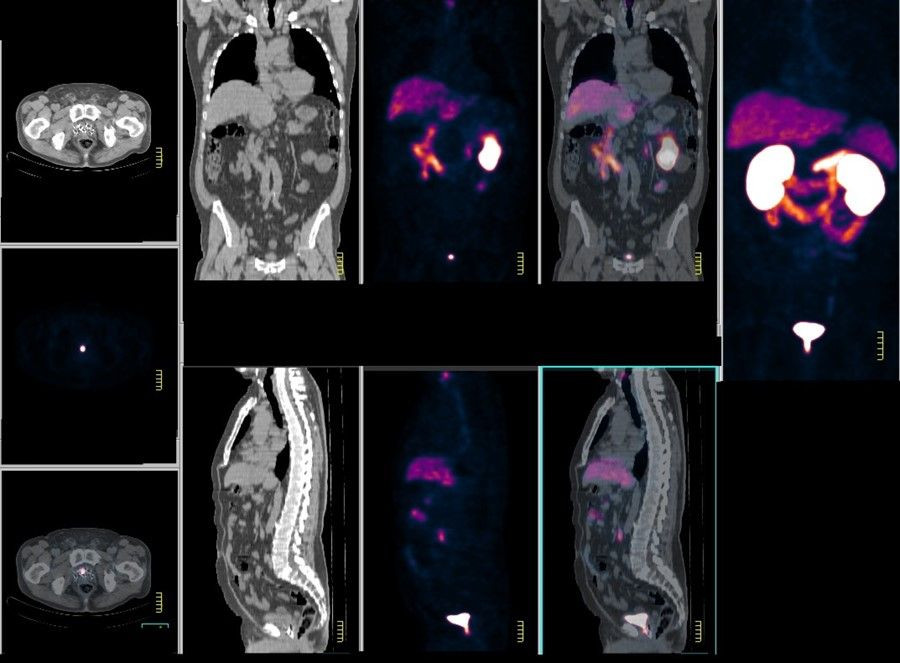

Actualmente, los hombres sospechosos de tener cáncer de próstata se someten a un análisis de sangre que detecta niveles elevados del antígeno prostático específico (PSA). Siguiendo el ensayo PRECISION dirigido por UCL, las pautas del Instituto Nacional de Excelencia Clínica (NICE), ahora también advierten que todos los hombres con un resultado de PSA positivo se sometan a una resonancia magnética antes de la biopsia, ya que se ha demostrado que esto distingue y aumenta mejor detección de cánceres agresivos mientras se reduce el sobrediagnóstico y el tratamiento innecesario de cánceres insignificantes.

Sobre esta base, los investigadores dicen que los marcadores genéticos recientemente descubiertos que predicen el riesgo de cáncer de próstata también podrían complementar una prueba de PSA y una resonancia magnética. Una prueba poligénica, que aún no está ampliamente disponible, puede identificar a las personas con genes (biomarcadores) de cáncer de próstata de alto riesgo y ayudar a predecir cuándo es probable que una persona comience a beneficiarse de la detección.

La vía de diagnóstico basada en la edad modeló un programa de detección en el que todos los hombres de entre 55 y 69 años recibirían una prueba de PSA cada cuatro años y, si la prueba era positiva, se realizaría una resonancia magnética y, si fuera necesario, una biopsia.

La vía adaptada al riesgo modeló un programa de detección en el que los hombres se someterían a una prueba de PSA (seguida de resonancia magnética y biopsia si fuera necesario) si y cuando su riesgo, determinado por su edad y puntuación de riesgo poligénico (perfil genético), alcanzara un cierto umbral.